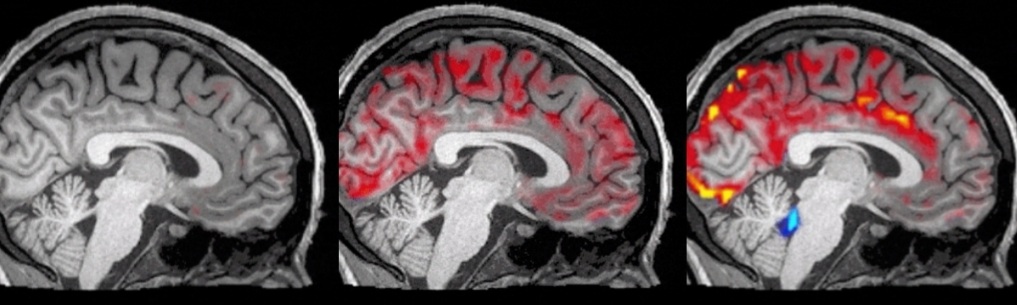

Scientists at Boston University took an unprecedented picture of the cleaning process: red is blood and blue is cerebrospinal fluid. What’s amazing is that it hasn’t been discovered before, and the blood will flow out of the brain periodically. Whenever a large amount of blood flows out, the cerebrospinal fluid takes the opportunity to launch a wave of attacks. The cerebrospinal fluid will remove toxins after entering the brain.

Such cleaning can only be done in your sleep, so you wake up with a refreshing brain; when you are not sleeping, the cerebrospinal fluid does not have a chance to get in to remove toxins. So, have sufficient sleep and don’t stay up late.

Source: Fultz et al 2019